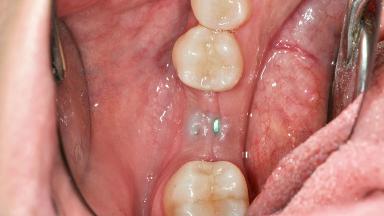

The patient, a healthy 38-year-old woman, was referred for increasing the width of the keratinized tissues at the buccal aspect of dental implant 46. The site exhibited a premature-closure screw exposure caused by trauma during chewing, with inadequate keratinized tissue.